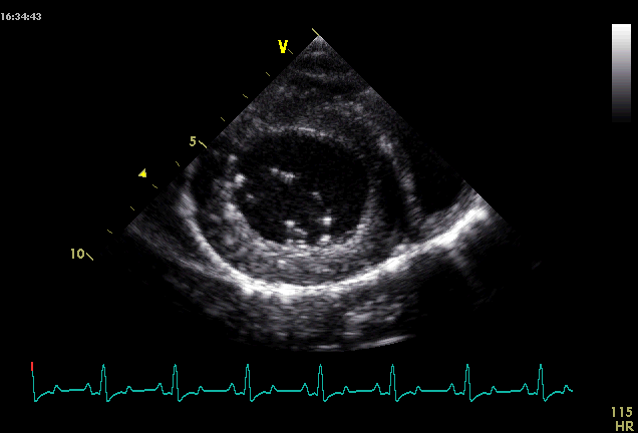

What view is this and at what level?

Right parasternal short axis view

LV @ pap mm level